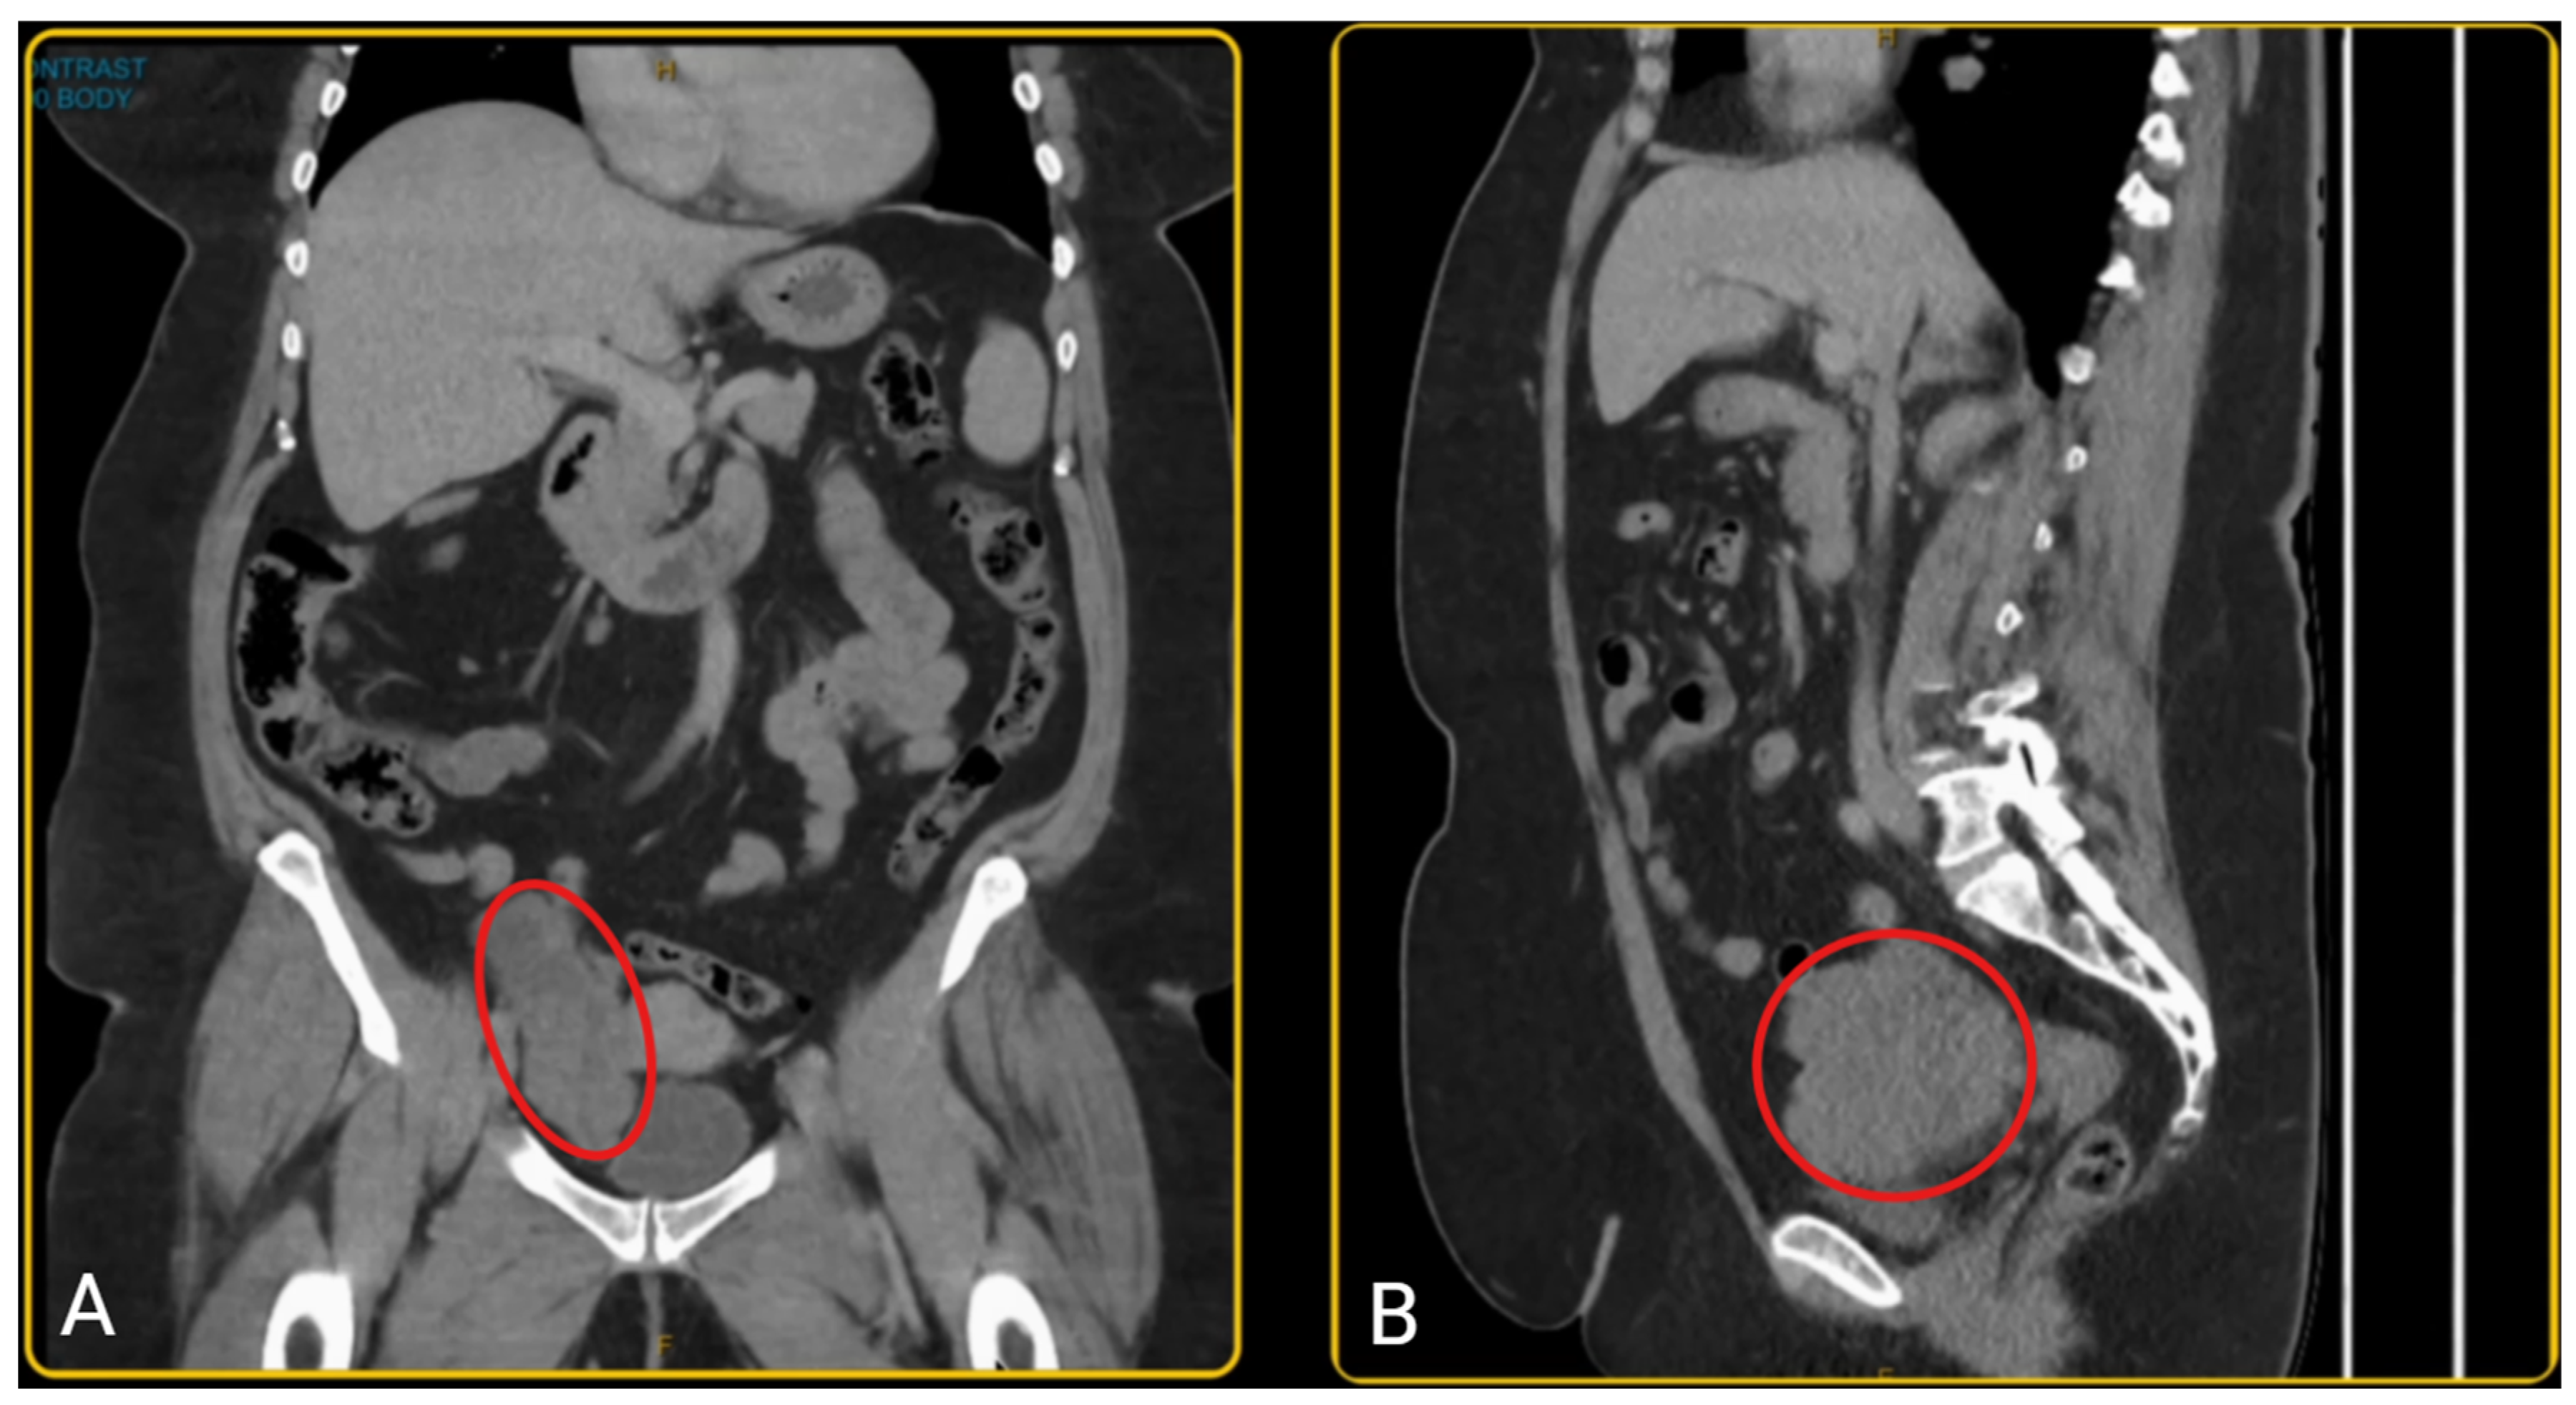

A woman in her late-50s presented with a history of post-menopausal bleeding and pelvic pressure. Pelvic ultrasound and CT scan showed a right adnexal mass with a solid component measuring 103 x 98 x 50 mm (Figure 1). However, her tumour markers were normal (CA 125 = 13; Ca 19-9 = 22; CEA = 2.5, AFP = 7; RMI = 111). She was pre-emptively diagnosed with an ovarian tumour, however since the diagnosis was not established, pre-operative biopsy was not performed due to risk of tumour seeding and technical challenges. Hence, the patient was planned for a diagnostic laparoscopy and laparoscopic oophorectomy.

Figure 1. A. Coronal view of pelvic CT scan; B. Sagittal view of pelvic CT scan showing right adnexal mass with a heterogenous composition measuring 103 x 98 x 50 mm.